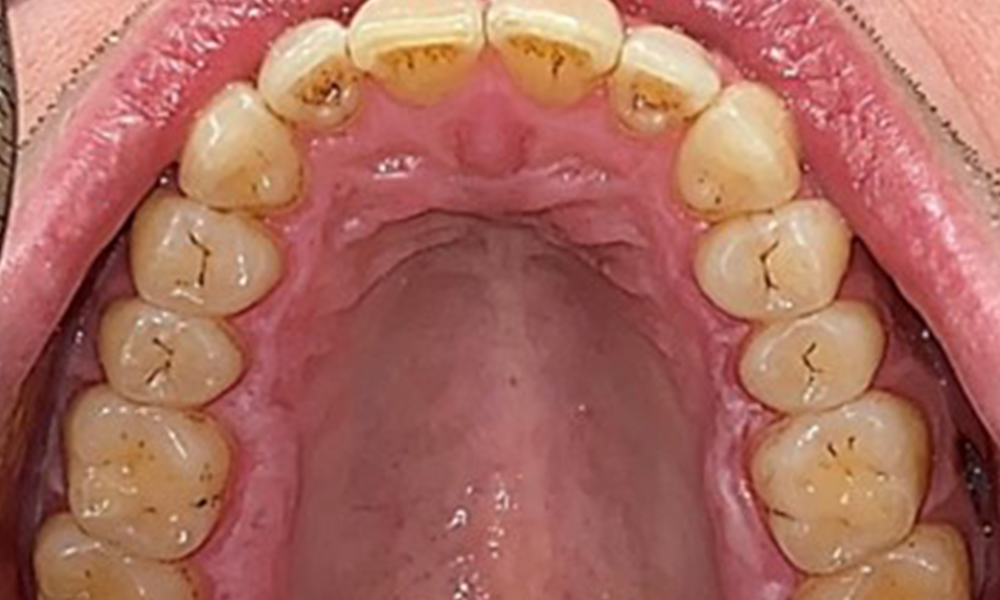

Observații la nivel dentar

Pacientul prezintă o dentiție completă, cu 28 de dinți. Se remarcă eroziuni și atriții. (Fig. 4, Fig. 5). Datorită bruxismului, timp de mulți ani, pacientul a purtat gutieră pe timp de noapte. Eroziunile sunt cauzate de consumul prelungit de băuturi izotonice. Nu au fost observate pierderi osoase de natură parodontală sau carii active.